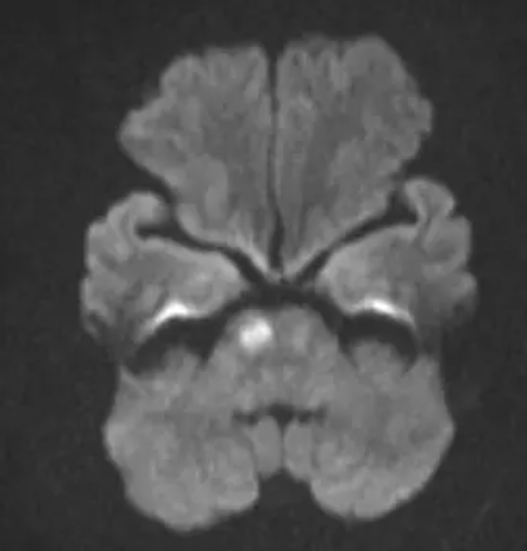

Nhận định ban đầu, các bác sĩ cho rằng, phản ứng qua trung gian miễn dịch của hệ thống đối với vết ong đốt gây ra co mạch và trạng thái tạo huyết khối kèm theo thiếu máu cục bộ dẫn đến đột quỵ. Vì vậy bệnh nhân được tiến hành chụp cộng hưởng từ sọ não ghi nhận nhồi máu cầu não phải. Người bệnh sau đó đã được xử trí tích cực và chuyển sang giai đoạn tập phục hồi chức năng tại Trung tâm Đột quỵ Phú Thọ.